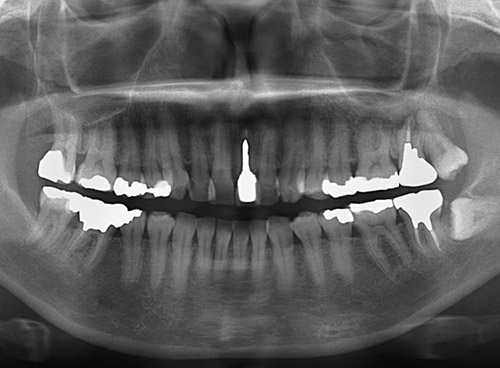

レントゲン診査は、コーンビームCTの代表格であるモリタ3DX FPD8にて行った。 1 は、根尖部に大きな透過像があり、クラックも存在するため、抜歯を計画した。そして、インプラント治療のメリット・デメリットを説明し、インフォームドコンセントを十分に行った。

図3 初診来院時パノラマX線写真。 -